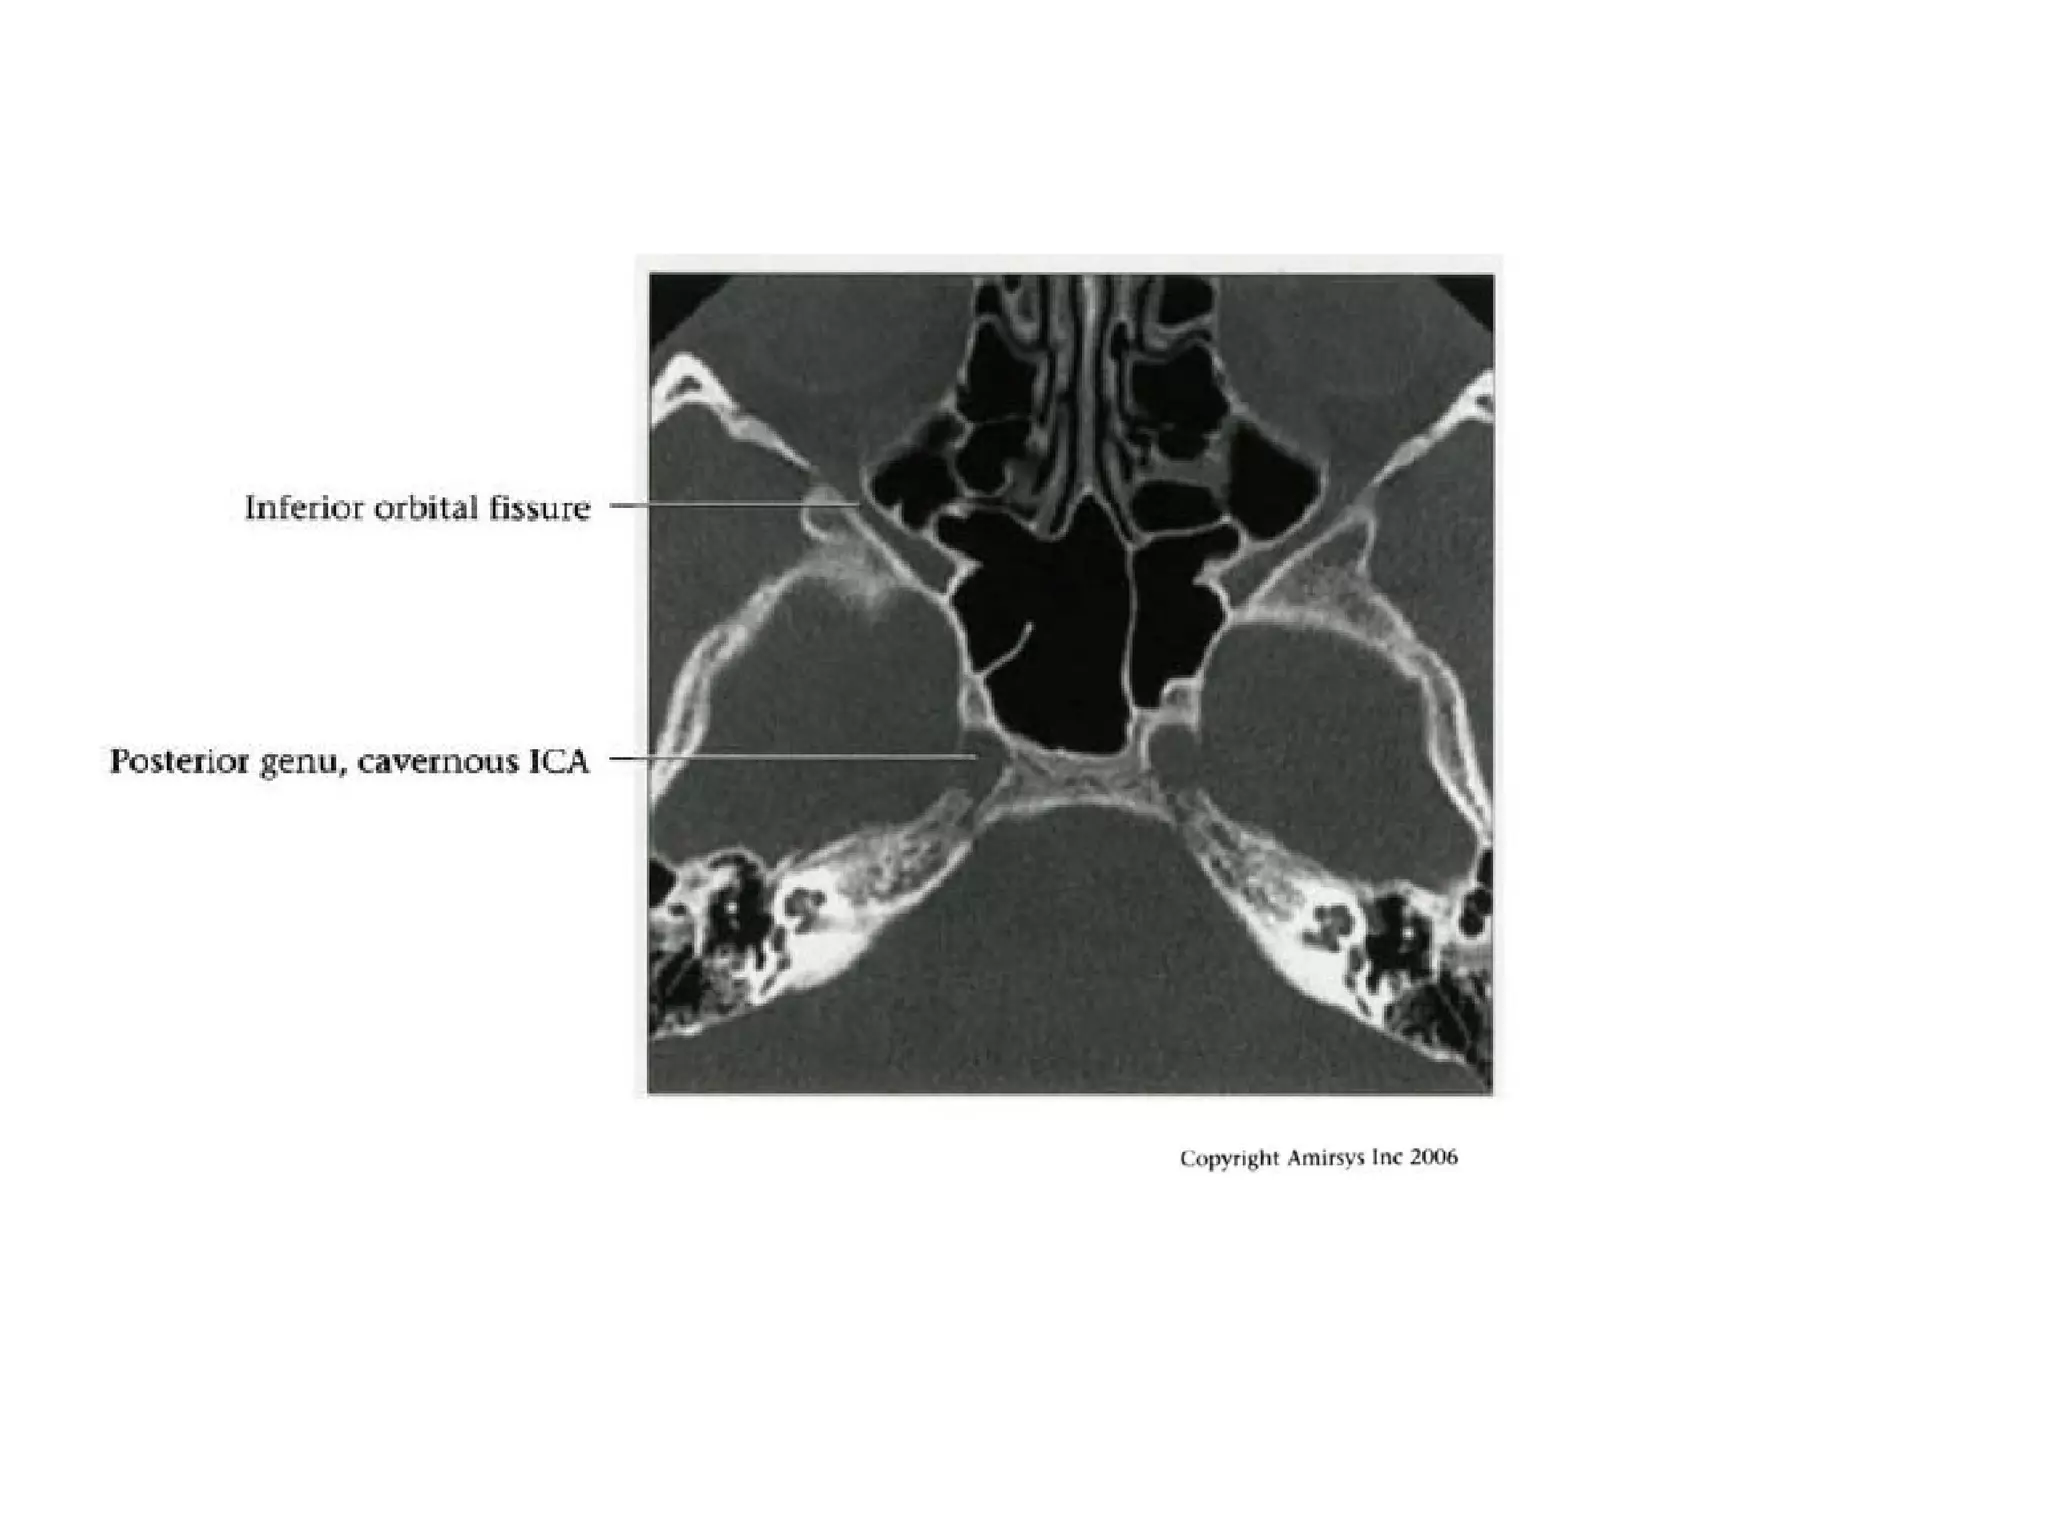

Cavernous (C4) segment

• Three subsegments joined by two genus (knees)

- Posterior vertical (ascending) portion

- Posterior (more medial) genu

- Horizontal segment

- Anterior (more lateral) genu

- Anterior vertical (subclinoid) segment

• Covered by trigeminal ganglion posteriorly

• Abducens nerve (CN6) is inferolateral

• Major branches

- Meningohypophyseal trunk (arises from posterior

genu, supplies pituitary, tentorium and clival dura)

- Inferolateral trunk arises from horizontal segment,

supplies cavernous sinus (CS) dura / cranial nerves;

anastomoses with ECA branches through foramens

rotundum, spinosum, ovale